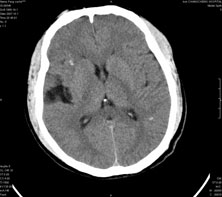

男,41岁,间断抽搐1小时,失神5分钟,bp130/90mmhg。低密度区ct值约16hu。

脑实质见多发散在的钙化点,左顶叶见一囊变灶,多考虑脑囊虫。

多发的囊泡(多发囊型)+多发的钙化(慢性钙化型)=混合型

支持;混合型脑囊虫病.请结合病史及补体结合试验.